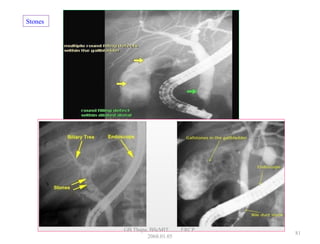

Stones

81